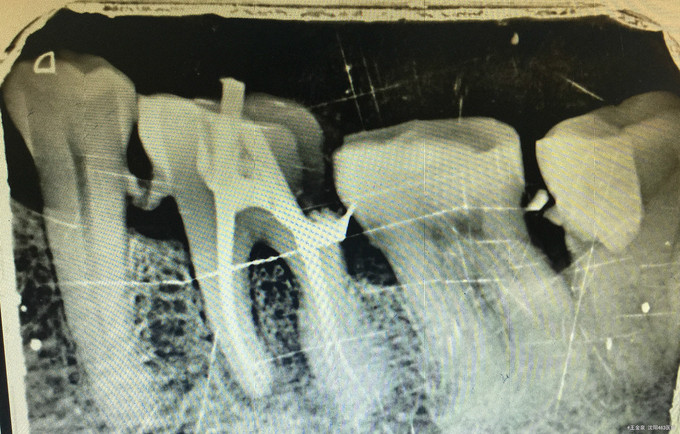

临床检查:36远中邻面龋坏,探疼(+),冷(++),叩(-)可探及穿髓点,无窦道,松动度(-),牙周正常. 辅助检查:X线示36远中龋坏累积髓腔。

诊断:36牙髓炎 治疗:经患者知情同意后,36局麻去腐降牙合,开髓拔髓寻找根管口,建立直线通路,扩通根管,确定工作长度。vdw/EDTA凝胶镍钛器械,低浓度次氯酸钠冲洗根管,预备至25/06,氢氧化钙诊间封药,一周后复诊,试主尖X线示恰充,试干根管,导AH-PLUS糊剂,VDW热压胶垂直加压根充,术后见根管恰充,暂封嵌体修复。